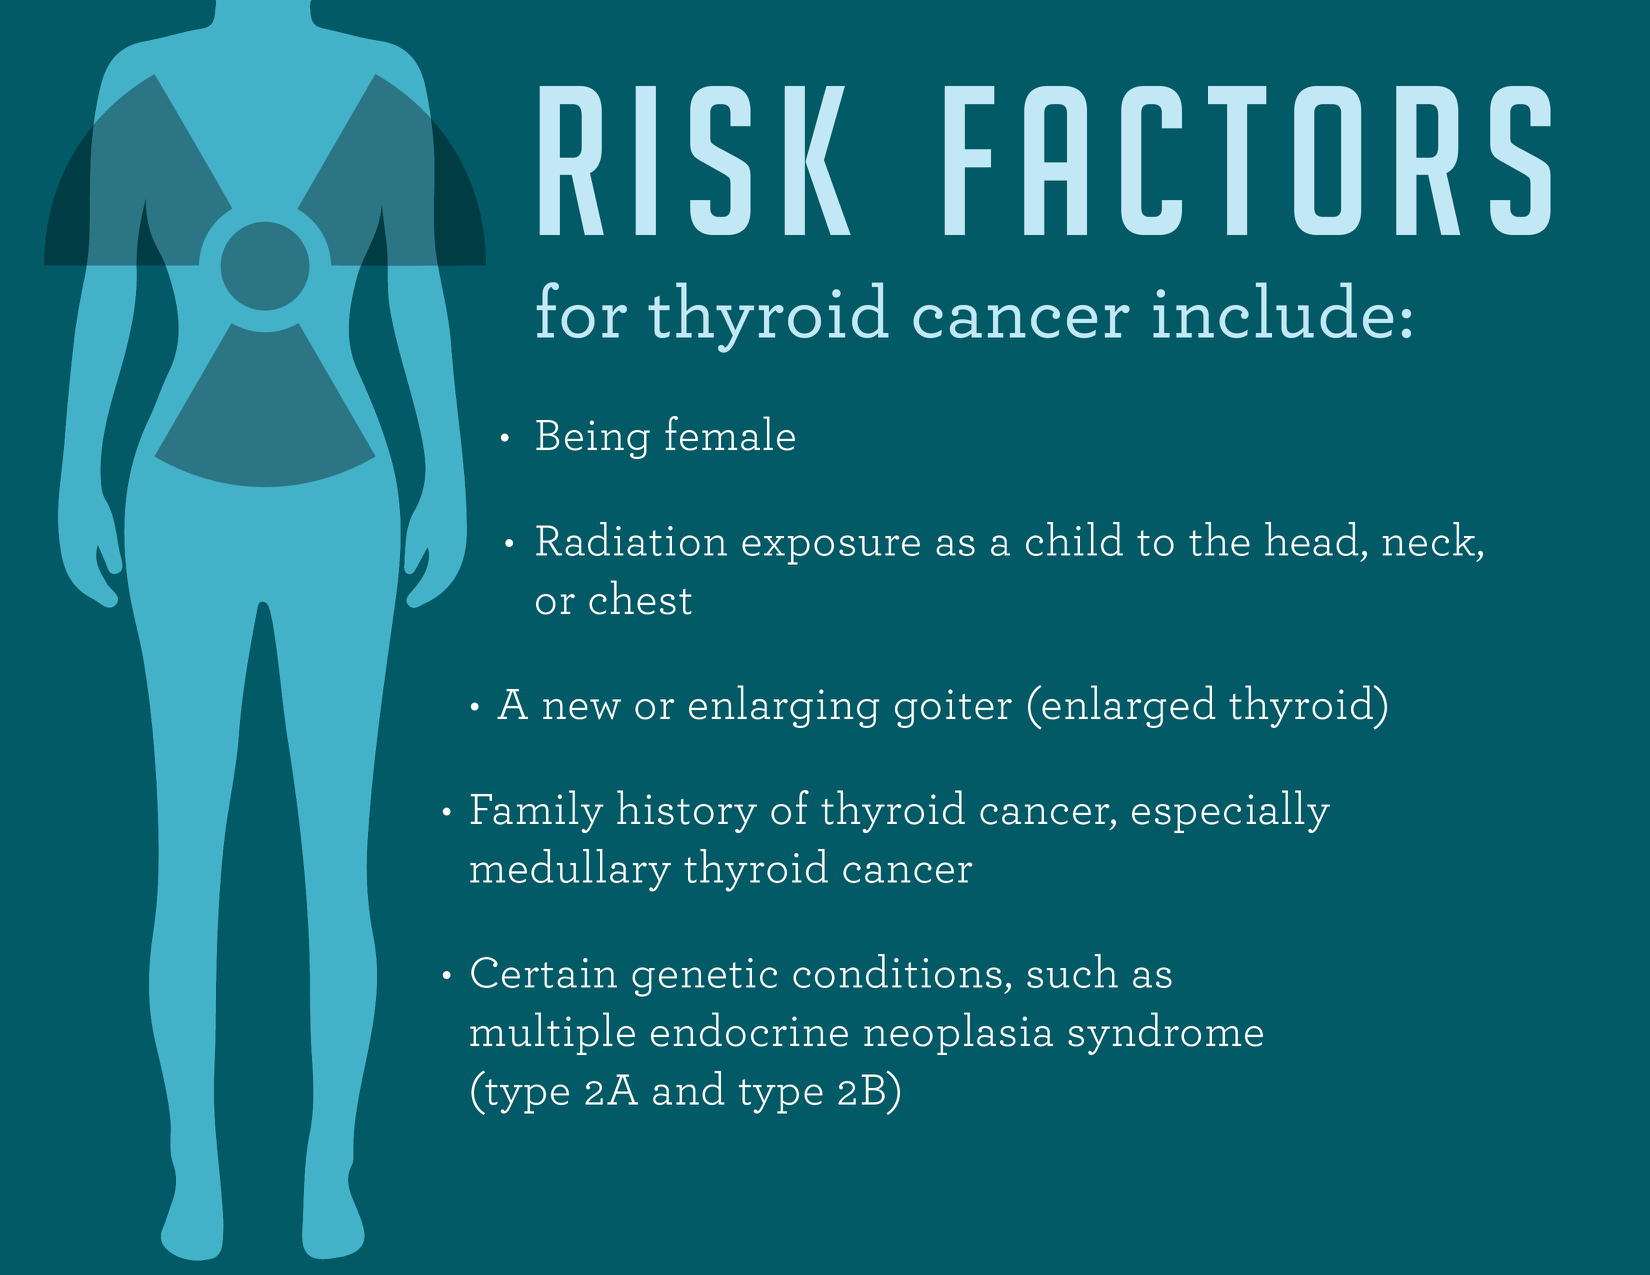

Cancers Free Full Text Thyroid Carcinoma A Review For 25 Years Of